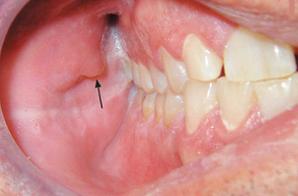

牙 咱们的腮腺导管口位于上颌第二磨牙牙冠颊侧的粘膜上(腮帮子),开口处的粘膜略隆起,常有唾液排出。但是好多人发现这个“肿物”竟然还会自己排出“液体”,顿时吓坏了。(图4)